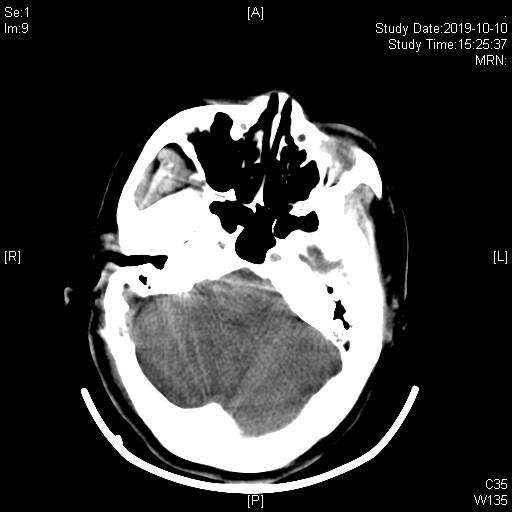

术后复查CT术区无出血,患者手术后立即停跳。

3D-TOF序列提示椎基底动脉迂曲,偏向右侧,小脑后下动脉PICA从劣势椎动脉发出,于上下各成一袢,最后绕回下方,呈“S”型。

TOF序列及FIESTA序列可见PICA在下方的第一个弯曲与面听神经关系密切。